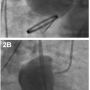

A 69-year-old male underwent a classic Bentall procedure for ascending aortic aneurysm at an outside institution. The patient had done reasonably well until 7 years later when he was admitted to an outside hospital with 2 weeks of fatigue and an episode of exertional dyspnea. Chest computed tomography angiogram revealed a large aortic root pseudoaneurysm at the left main coronary artery with pericardial hematoma (Figure 1). The patient was transferred to our institution for further workup. Aortography performed at our institution

confirmed the findings (Figures 2 and 3; Videos 1-3 available at www.invasivecardiology.com). The patient underwent a successful operative repair of the pseudoaneurysm and was discharged home 8 days later.